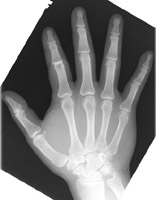

- Click on the image for a larger versionAPA radiograph of the hand. The second PIP joint is slightly overriding.